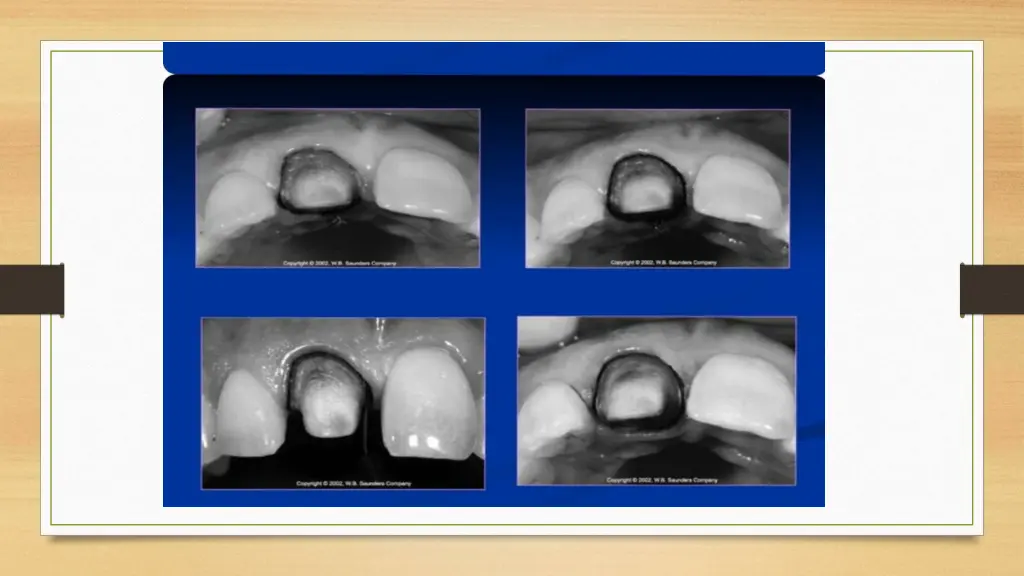

CLINICAL PROCEDURE The Supra-gingival & Sub-gingival margins are very simple to place but the sub-gingival margin placement is rather difficult. So, Prior the placement of margin sub-gingivally the preparation should be extended to the free gingival margin facially & inter-proximally. The steps are as follows:

TISSUE RETRATION For protection from abrasion 2) For proper access BY GINGIVAL RETRACTION CORDS For Rule 1 Margin 2 Cords are used 1 cord is placed 0.5mm below the prepared margin. 2nd Cord is displaces the first cord apically & sits b\w the margin & tissue.

For Rule 2 Margin 1) 2 Large diameter Cords are used. Thick cord is placed for impression. 2) Electro-surgery is necessary to remove overhanging tissues.

This process: 1) Protects the tissues 2) Creates the correct axial reduction Establishes a desired sub-gingival level margin.